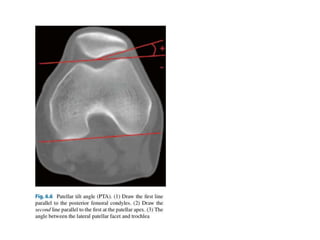

Imaging of the patellofemoral joint

AP and lateral knee x ray

Axial - Merchants view and Laurin view

MRI axial view

CT rotational profile

The knee skyline

Merchant view is a

superior-inferior projection of the

patella it is one of many different

methods to obtain an axial

projection of the patella. This is

an ideal projection for patients

that are better suited in the

supine position.

The knee skyline Laurin

view is an inferior-superior

projection of the patella. It is one

of many different methods to

obtain an axial projection of the

patella. This projection is best

suited to patients able to

maintain a semi-recumbent

position on the examination

table.

Congruence Angle

CT classification of malalignment

Type 1 - lateral subluxation without tilt

Type 2 - lateral subluxation with tilt

Type 3 - lateral tilt without subluxation

Type 4 - radiographically normal alignment